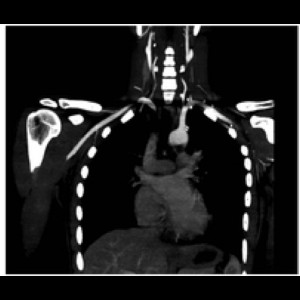

Misdiagnosis of subclavian artery stenosis: the importance of dynamic manoeuvre

Misdiagnosis of subclavian artery stenosis: the importance of dynamic manoeuvre

Misdiagnosis of subclavian artery stenosis: the importance of dynamic manoeuvre

Misdiagnosis of subclavian artery stenosis: the importance of dynamic manoeuvre